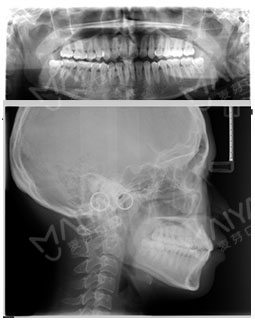

2016年8月8日 到麦芽进行口腔检查

2016年8月8日,经过朋友的劝说,我加入了正畸的行列,我的牙齿上下颌前牙前突咬合不是很好,导致脸型也不是很好看。我对舒适感要求很高,带隐形的完全看不出来。所以选择透明隐形的隐适美。还是私人定制款,嘻嘻。今天来记录我的矫正经历,跟大家一起分享一下,同时给自己留个回忆。我之前就和这边的医生预约好,我很准时的来医院。先是给我拍牙齿的片子,牙齿牙列不齐,幻想着矫牙后的模样~ 相信麦芽的技术!